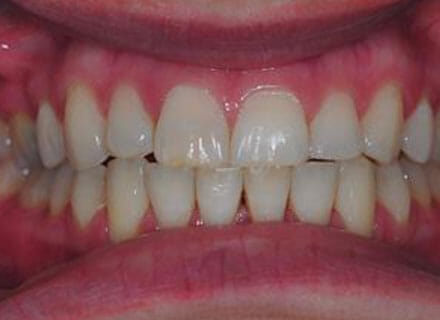

In this case the whole smile was affected by a tooth that was missing (a visible gap or hole at the side when smiling) and a tooth at the front that had grown the wrong side of the bite. We were able to correct the gap at the back by pulling the tooth behind forwards into the gap left by the previous extracted tooth. The clear brace also pushed the tooth at the front back in to the right position and the smile was massively improve. This case took around 18 months to complete.